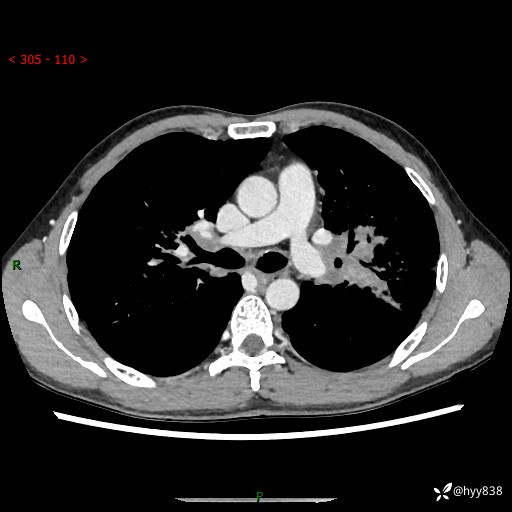

中年男性,咳嗽咳痰1月余。细看:肺、肺门、气管,貌似都有问题---(有结果)

现病史:患者于1个月前受凉后出现间断性咳嗽,伴白色泡沫样痰,无发热寒战、咯血、胸痛胸闷、恶心呕吐、呼吸困难等特殊不适,起初未予特殊处理,后患者就诊当地中医医院,查胸部CT提示支气管炎并双肺感染性病变,经抗感染(哌拉西林舒巴坦),止咳化痰(溴己新、三拗片)等治疗后,患者自诉咳嗽咳痰症状较前缓解,未诉发热等其他特殊不适,近期复查CT提示“肺部感染灶未见消退,双侧肺门增大,双肺散在小结节”,今为求进一步诊治,前来我院就诊,门诊以“肺部感染”收住入院。 患者自起病来精神、食欲、睡眠尚可,大小便正常,体力、体重无明显变化。

胸部CT平扫+增强(两期)